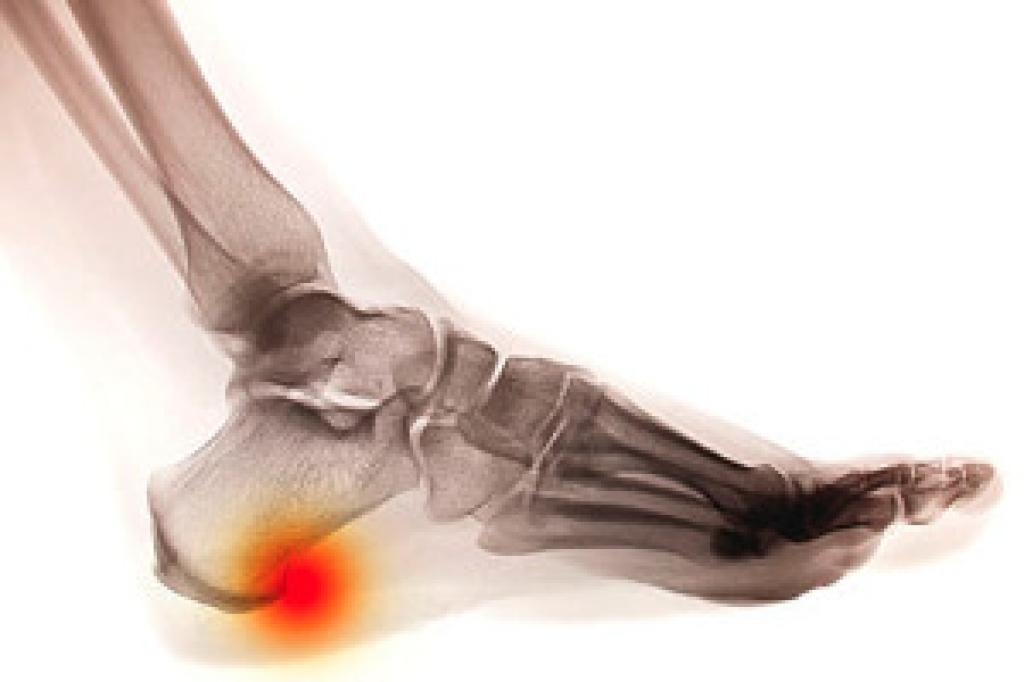

Foot and ankle surgery is generally reserved for cases in which less invasive, conservative procedures have failed to alleviate the problem. Some of the cases in which surgery may be necessary include:

- Removing foot deformities like bunions and bone spurs

- Severe arthritis that has caused bone issues